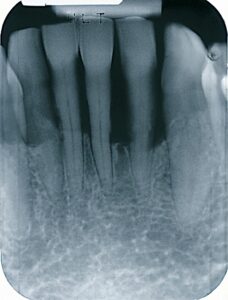

Periodontitis is one of the most common infections i USA and Europe. It is a chronic disease, were there is an active and an inactive phase. At first and if there is no pain the bone will break done. Later the teeth will loosen and hurt. Futhermore the disease can cause bad breath and change the look of the smile. The goal with treatment is to keep the teeth and replace missing teeth fx with implants.

If plaque is not removed, it will cause the gums to bleed, a condition called gingivitis. Unremoved plaque can devolop into a hard substance called calculus (tartar). As plaque and calculus build up, the gum and bone anchoring the teeth in the jaw will be destroyed – this is irreversible. Eventually, there will not be enough gum and bone remaining to hold the tooth in place, and the tooth will need to be removed.

If plaque is not removed, minerals in saliva combine with plaque at the tooth surface and harden into rough mineral deposits, calculus (tartar, hard build-up). Calculus will develop in less than two days both over and under the gum-line and bacteria will stick to it. Toothbrush and floss can’t remove calculus. It can only be removed with special instruments at the dental office. If it is not removed periodontal disease will occur.

Bacteria produce toxins (poisons) that irritate the gum, cause infection, start the inflammatory process and destroy the bone and fibers around the tooth. The body’s immune system response sometimes over-reacts leading to further bone damage.

The gum draws back from the tooth (creates a pocket) and allows more bacteria to enter. If untreated the pocket gets deeper, the bone is destroyed, the teeth loosen and need removal. In addition these bacteria and the inflammation process can travel throughout the body. Research has linked periodontal diseases to preterm, low birth weight babies, cardiovascular disease and diabetes. Often, this destructive process has mild or undetected symptoms.

Mild Periodontitis: When gingivitis is untreated, the breakdown of supporting bone and tissue proceeds, the space around the tooth deepens. The sulcus is now called a pocket. The depth of the pocket is measured carefully, and provides information as to the stage of the disease. (“Mild” 1-2 mm loss of attaching fibers and bone – called Clinical Attachment Loss – Usually seen with 5 mm pockets).

Moderate to advanced Periodontitis: The plaque and its byproducts attack further, causing more of the fibers and bone support to be lost. The tooth might loosen, and the root may become exposed and sensitive. Unless treated, the tooth may fall out or need to be removed. (“Moderate” 3-4 mm or “Advanced” 5 mm or higher Clinical Attachment Loss – Usually seen with 6 mm pockets or higher).